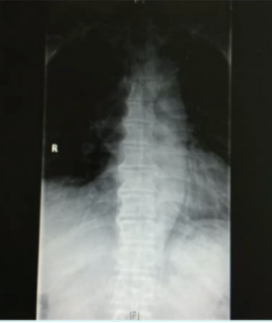

胸椎X线检查:多个胸椎只有右侧缘肥大骨赘骨桥形成

相对而言,这个病例倒是比前者“实诚”很多,虽然患者有腰背部疼痛的症状,但是检查结果既没有炎性指标的升骶髂关节也无明显异常,唯一特别的是患者胸椎的X线改变。

但诊断其实也没那么难,从患者的侧位X线可以看出其并不是AS特征性的骨桥形成(即接近垂直状态),正位X线中也可以看出其并非是对称性的竹节样改变,该名患者的多个胸椎只有右侧缘肥大骨赘骨桥形成。